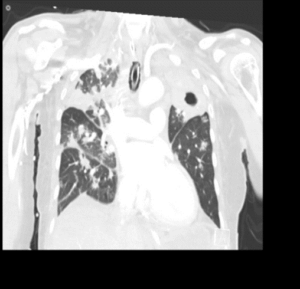

CASE 5 –A 57-year-old woman presented to the emergency department with fevers, cough and night sweats and recent weight loss. She arrived in Australia from Philippines 5 days previously. In the ED she had significant respiratory distress requiring high flow oxygen and subsequent intubation and ventilation as her respiratory failure progressed.

EXPLANATION -There is diffuse bilateral consolidation more prominent in the upper lobes.

There is left upper lobe cavitation. Bilaterally there are pleural effusions.